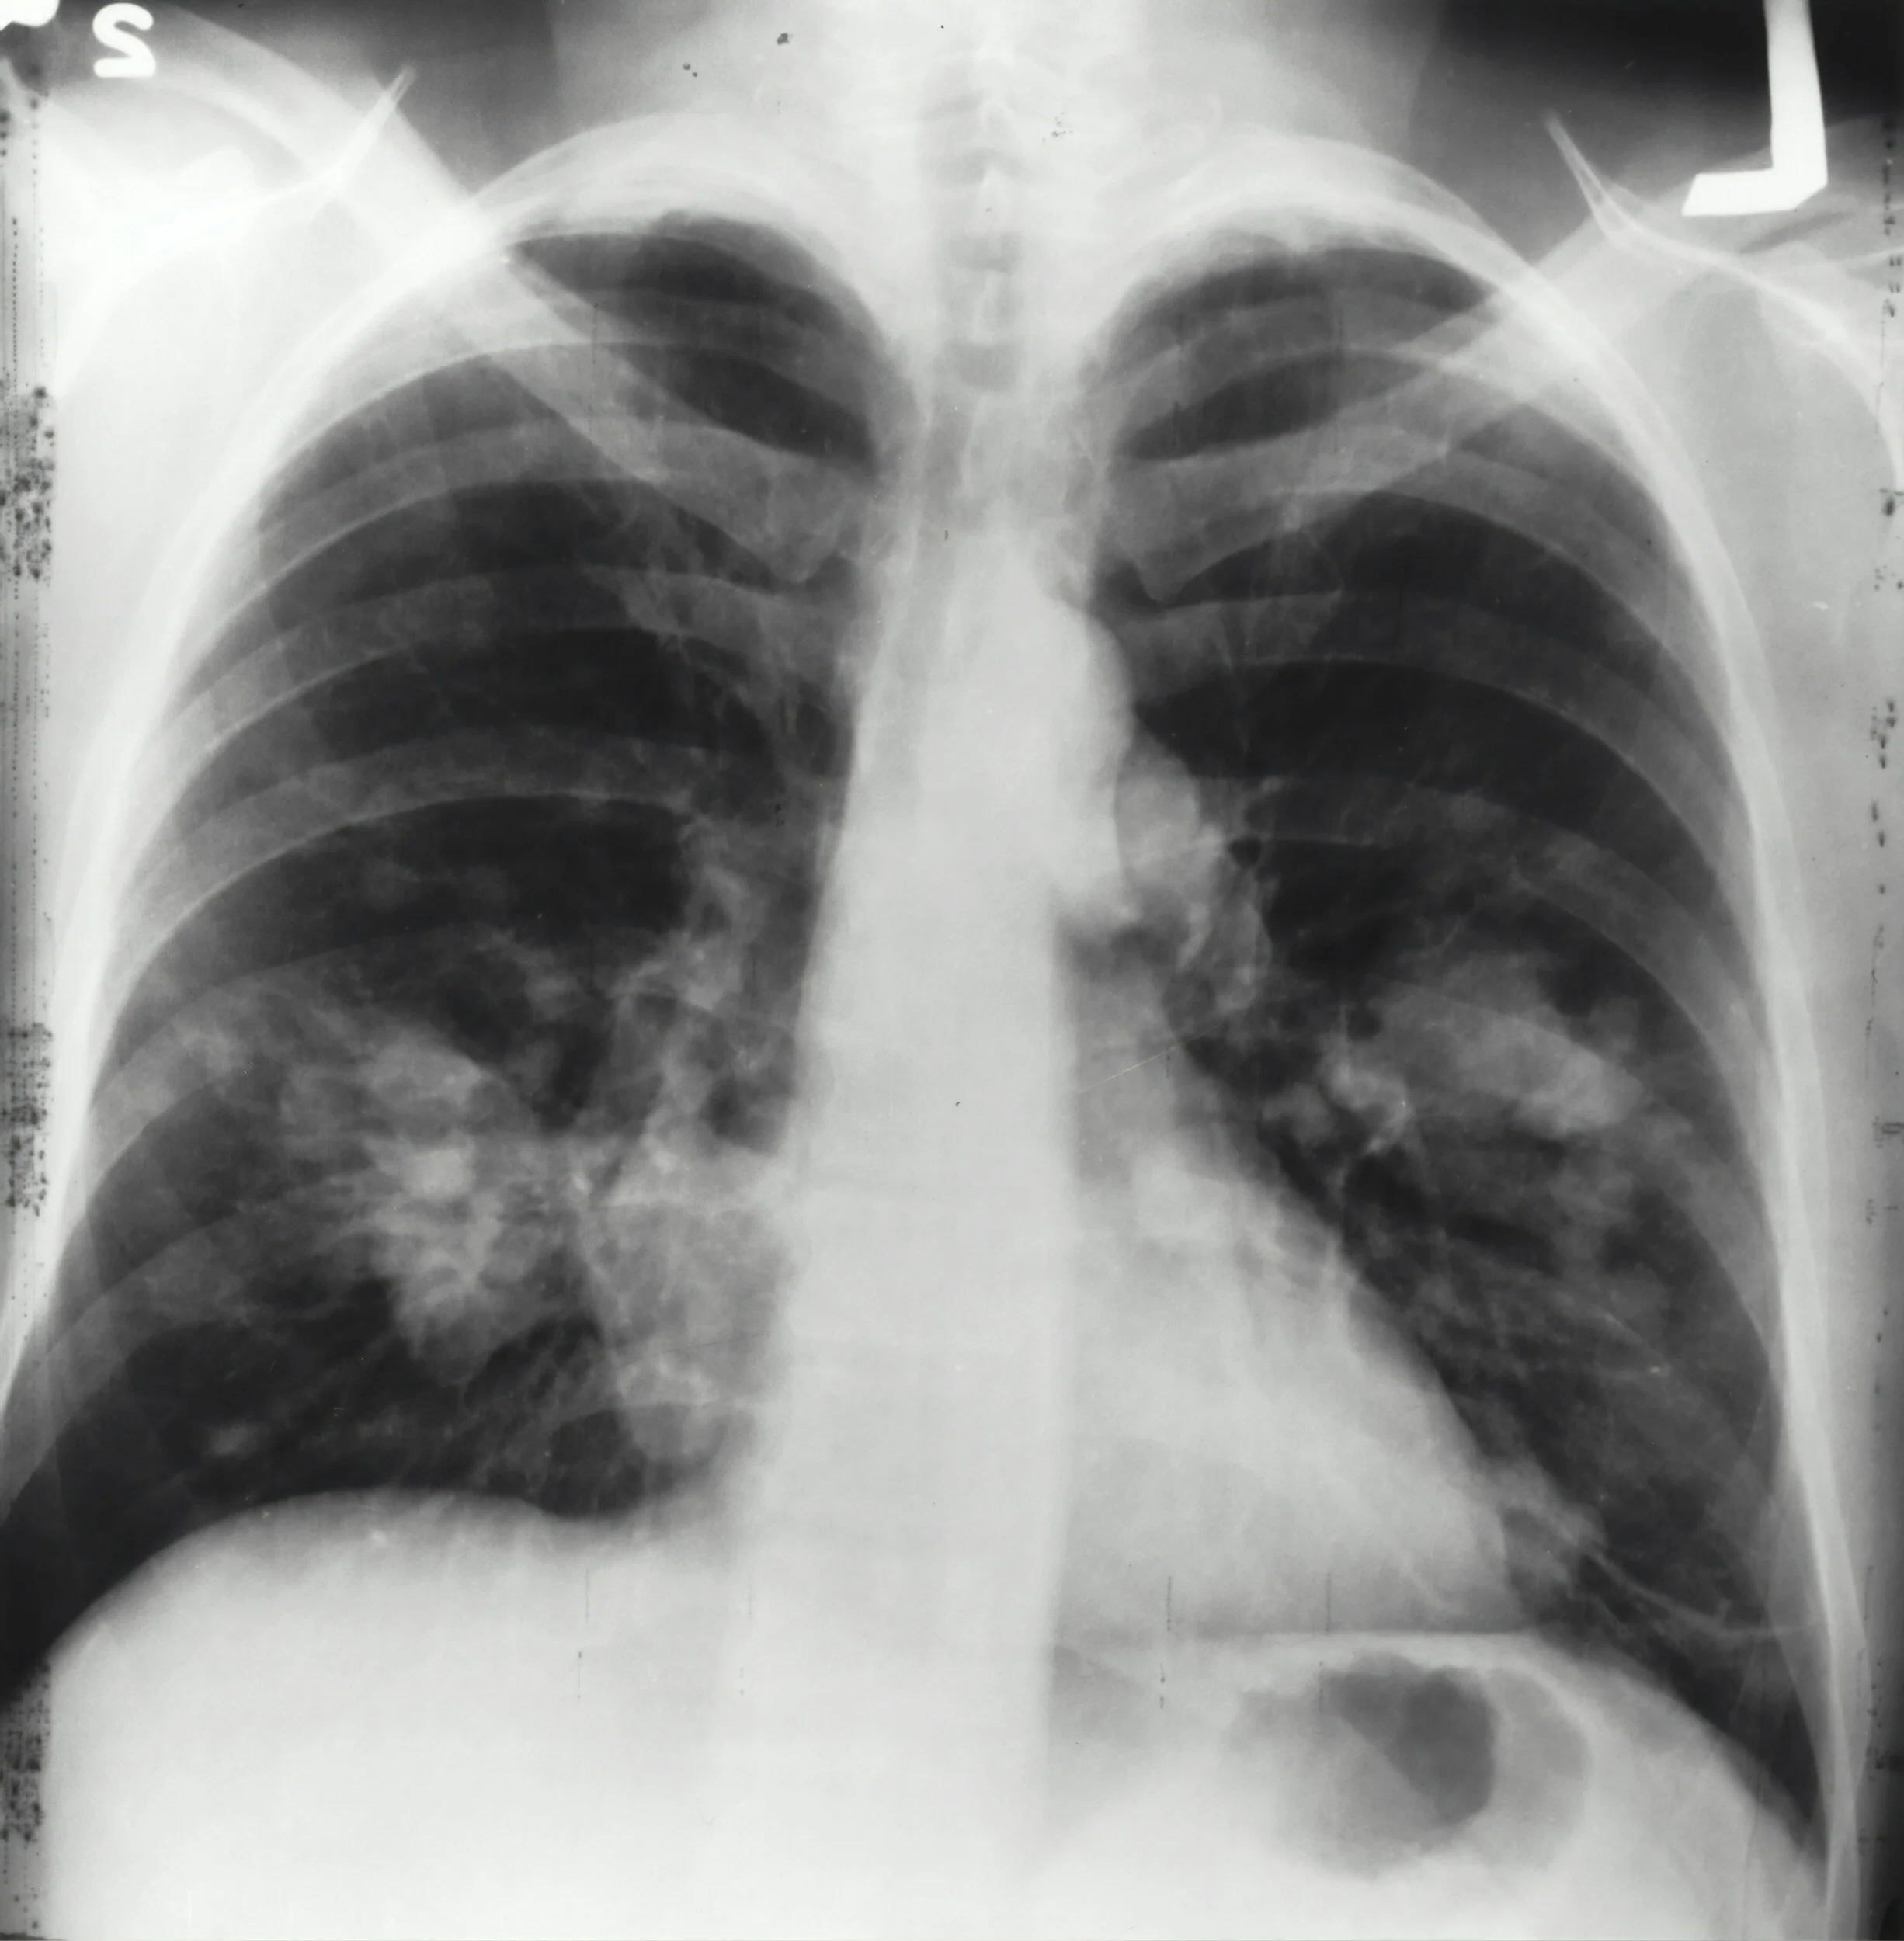

Aspiration-related symptoms could develop immediately after the event to a few days later. Immediate symptoms may include difficulty breathing and wheezing, which is more likely to occur for solid boluses or large-volume aspiration. The symptoms that develop 24-48 hours after an aspiration event are usually related to pneumonia or associated respiratory conditions and may include dyspnea, increased work of breathing, tachypnea, chest pain, and congestion.

So, suppose Jacob is aspirating for a couple of weeks without developing these symptoms. In that case, he is, at least currently, safely aspirating without adverse reactions. This could change, but it's a good indicator that he may continue to do well and that the benefits may outweigh the risks of resuming his current diet.